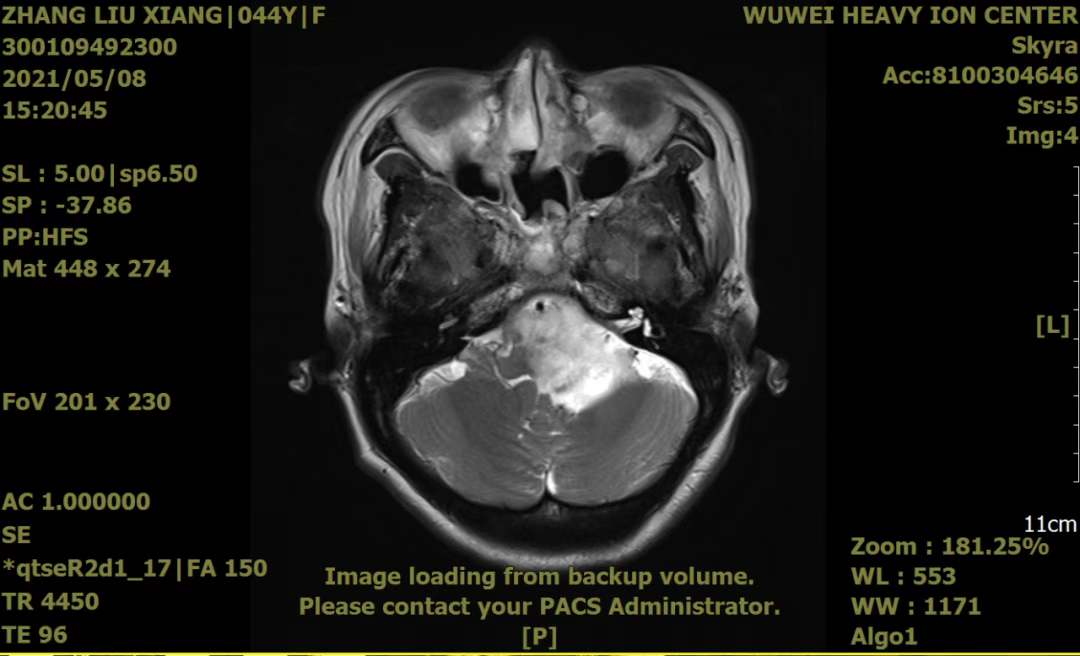

这个故事要从五年前说起,一场突如其来的疾病打破了张女士原本平静而幸福的生活,张女士被诊断为“脑胶质瘤”,并在南昌大学第二附属医院全麻下行了“经鼻窦垂体瘤切除术”。不料,却在术后一年又出现了恶心呕吐、头痛头晕,“复发”使张女士陷入无尽的痛苦、绝望,就在她和家人倍感无助、无望时,偶然看到关于重离子的一则报道,这不由得让张女士及家属燃起了一丝希望,他们立即与重离子中心马有国副院长取得联系,在马院长耐心细致的讲解后,跨越两千多公里,从老家飞到武威,来到了甘肃省武威肿瘤医院重离子中心放疗一科。经重离子专家团队会诊后,给予了碳离子治疗,DT:48GyE/16f,同步给予脱水、保肝、保护胃黏膜,营养等对症支持治疗,同时注重患者的心理疏导,帮助其树立抗癌信心,经过系统的治疗,患者病情好转,病灶较前明显缩小,生活质量显著提升。于2025年05月08日患者再次来院复查,病情平稳,精神状态良好。

治疗前